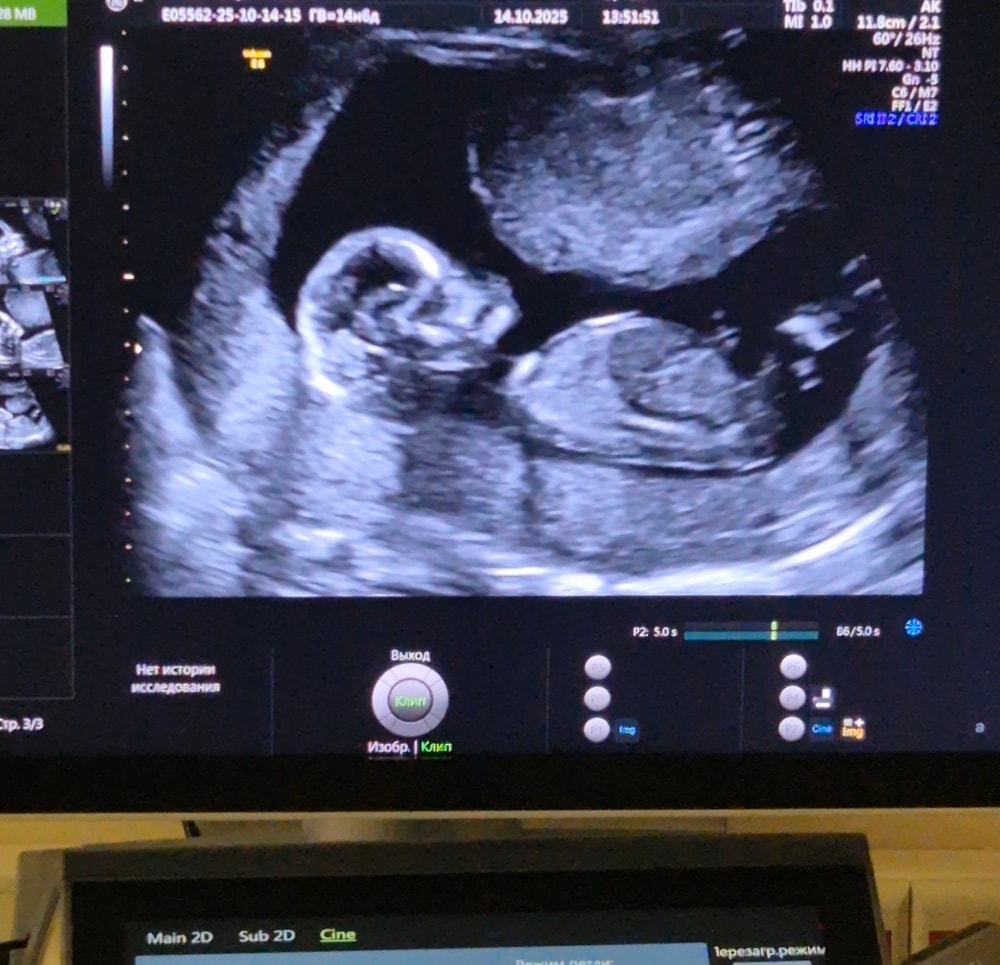

УЗИ на 11 неделе

Анализы, скринингиДевочки, это нормально, что расположение такое? Или это такой ракурс? 10.6 недель по ктр

Нормально ли, что он лежит горизонтально?

Если Вы об этом, то да, нормально :)

Анжелика , да, об этом) спасибо, врач хотела, чтобы было красиво, сказала непоседа, не лежит нормально и тут у меня закралось сомнение, нормально ли это, что он так лежит

Это норма, что они пока в горизонтальном предлежании)

Сроки пока маленькие)

Анжелика , у вас немного по-другому, а у меня прям спинкой получается, а вот то, что за ножками, я так понимаю, это жёлтый мешок?

Да, может быть ЖМ. В скором времени он исчезнет.